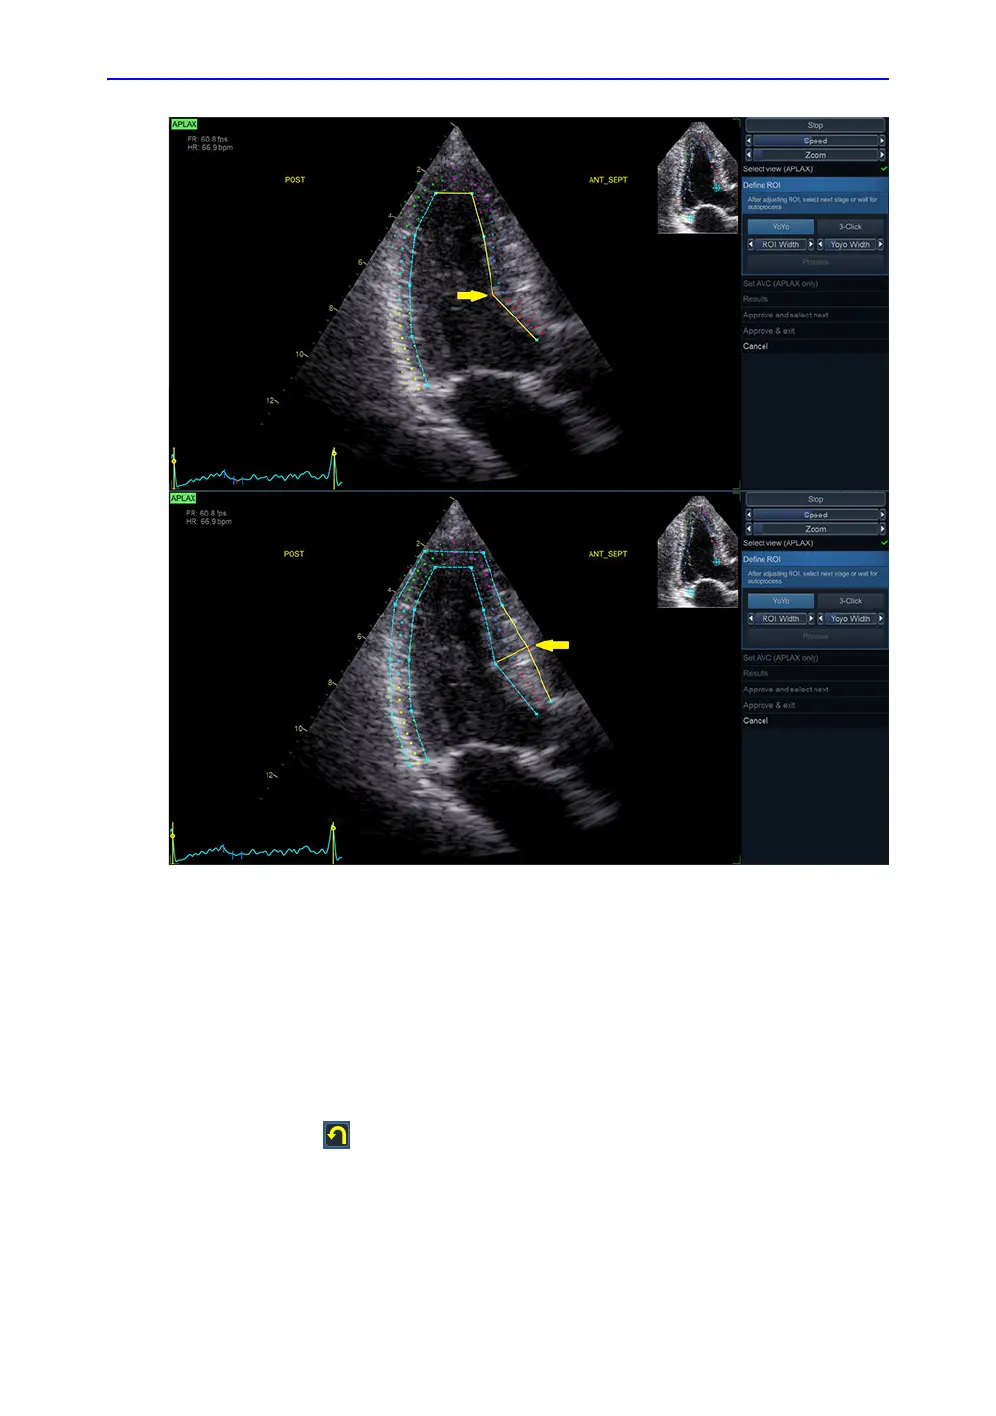

Figure 8-14. ROI Editing Options

To create a new ROI

The system automatically displays a frame where the

endocardial border is usually clearly visible. To use another

frame, while in Define ROI stage, pause the playback by

pressing Stop. Then, use the Frame slider to select a different

frame for ROI definition.

To create a new automatic ROI, click the Reset stage symbol

. This relaunches the automatic segmentation.

Sometimes the automatic ROI may fail to capture the correct

ROI. In this case, a 3-Point ROI alternative is provided.

NOTE: The 3-Point ROI is the standard ROI method for TEE data and

Pediatric exams.